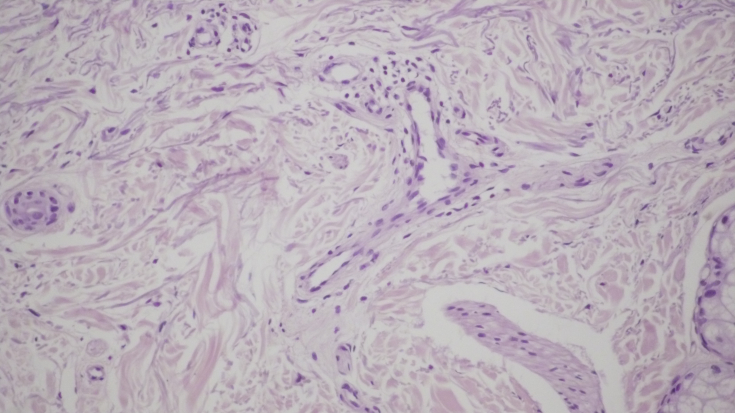

За даними інструментального дослідження, в комбінованій схемі апаратно-ін'єкційного ефекту зникла лімфоїдно-клітинна інфільтрація дерми, що свідчить про чітку синергію обраних методик в схемі комплексного anti-age рішення для вікової шкіри.

Мал. 3. Морфологічна картина шкіри перед проведенням лікувальних заходів: виражена вогнищева запальна інфільтрація дерми, х200; запальна інфільтрація навколо волосяних фолікулів, ознаки фіброзу, х200; проліферація дрібних судин капілярного типу з периваскулярної лімфоїдно-клітинною інфільтрацією, х200;

Мал.4. Ізольований радіохвильовий вплив на шкіру. Збереження запальних елементів на фоні зниження лімфоїдно-клітинної інфільтрації дерми при вогнищевій проліферації фібробластів, х200.

Мал.5. Комбіноване введення пептидного препарату і радіохвильового впливу на шкіру. Відсутність лімфоїдно-клітинної інфільтрації дерми з вогнищевою проліферацією фібробластів, х200.